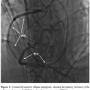

At the time of his presentation, the patient was found to have a blood pressure of 90/50 mm Hg and a heart rate of 110 bpm in sinus rhythm. Vasopressors and inotropes were adjusted and we started the procedure by placing a right radial artery 6 Fr sheath. During coronary angiography, the standard 5 Fr Judkins left (JL) 3.5 catheter failed to selectively engage the ostium of the Cabrol conduit, so we changed to an Amplatz left (AL) 2 catheter, which enabled a better cannulation. After extensive catheter manipulation, the 6 Fr AL 2 catheter engaged the Cabrol conduit ostium slightly better and the first angiograms showed a diffuse stenosis of the Gore-Tex graft to the left main starting at the site of the coronary aorta-anastomosis with impaired distal flow around the left coronary system (Figures 2A and 2B). Then, the saphenous bypass graft to the right coronary artery was cannulated, showing its patency (Figure 3).